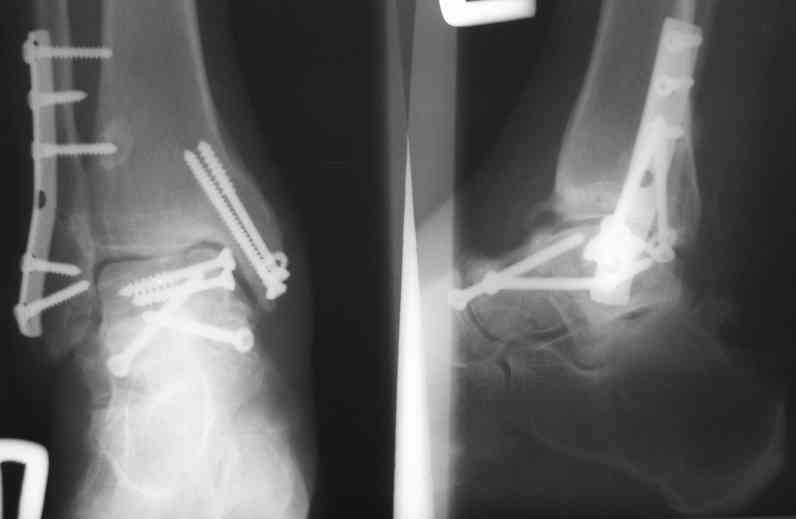

Случай с множественным оскольчатым переломом тарана оперированный из двойного доступа.

Через 2 мес.:

Через 8 мес.:

Через 14 мес.:

И второй случай из недавней ташкентской практики, (извините за качество ренгенограммы и только в одной проекции) случай падения с высоты (кстати моего друга - известного киноактера) - открытый

смещенный перелом тарана, с переломом переднего края дистального эпиметафиза большеберцовой кости.

При поступлении в приемной сделана первичная обработка с ушиванием открытой латеральной раны и вытяжением за пятку.

Из-за отсутствия времени пришлось оперировать на второе утро, из материала, что имеем на месте, фиксирован двумя шурупами, а третий-это контур сломанного жойстика в 4 мм. На дистальный медиальный конец тибиа antiglide 3.5 мм пластина. Через пару дней выписан и несмотря на предупреждение, самостоятельно начал нагрузку в 4 недели, время не ждет, снимается в боевике в Росийской Федерации.

Решили не связываться с остеосинтезом, а сделать сразу берцово-пяточный блок. Снимки в приложении.

По завершении удлинения, наверно, заштифтуем.

Комментарии/критика приветствуются.